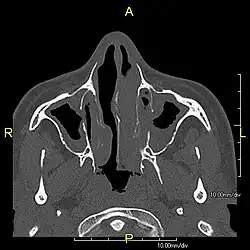

Around 80% of people with primary ciliary dyskinesia experience respiratory problems beginning within a day of birth. Many have a collapsed lobe of the lung and blood oxygen low enough to require treatment with supplemental oxygen.[1] Within the first few months of life, most develop a chronic mucus-producing cough and runny nose.[1] The main consequence of impaired ciliary function is reduced or absent mucus clearance from the lungs, and susceptibility to chronic recurrent respiratory infections, including sinusitis, bronchitis, pneumonia, and otitis media. Progressive damage to the respiratory system is common, including progressive bronchiectasis beginning in early childhood, and sinus disease (sometimes becoming severe in adults). However, diagnosis is often missed early in life despite the characteristic signs and symptoms.[2] In males, immotility of sperm can lead to infertility, although conception remains possible through the use of in vitro fertilization, there also are reported cases where sperm were able to move.[8] Trials have also shown that there is a marked reduction in fertility in females with Kartagener's syndrome due to dysfunction of the oviductal cilia.[9]

Many affected individuals experience hearing loss and show symptoms of otitis media which demonstrates variable responsiveness to the insertion of myringotomy tubes or grommets. Some patients have a poor sense of smell, which is believed to accompany high mucus production in the sinuses (although others report normal – or even acute – sensitivity to smell and taste). Clinical progression of the disease is variable, with lung transplantation required in severe cases. Susceptibility to infections can be drastically reduced by an early diagnosis. Treatment with various chest physiotherapy techniques has been observed to reduce the incidence of lung infection and to slow the progression of bronchiectasis dramatically. Aggressive treatment of sinus disease beginning at an early age is believed to slow long-term sinus damage (although this has not yet been adequately documented). Aggressive measures to enhance clearance of mucus, prevent respiratory infections, and treat bacterial superinfections have been observed to slow lung-disease progression. The predicted incidence is 1 in approximately 7500.[10]

Diagnosis

Several diagnostic tests for this condition have been proposed.[5] These include nasal nitric oxide levels as a screening test, light microscopy of biopsies for ciliary beat pattern and frequency and electron microscopic examination of dynein arms, as the definite diagnosis method. Genetic testing has also been proposed but this is difficult given that there are multiple genes involved.[6]

When accompanied by the combination of situs inversus (reversal of the internal organs), chronic sinusitis, and bronchiectasis, it is known as Kartagener syndrome[3] (only 50% of primary ciliary dyskinesia cases include situs inversus).[11]